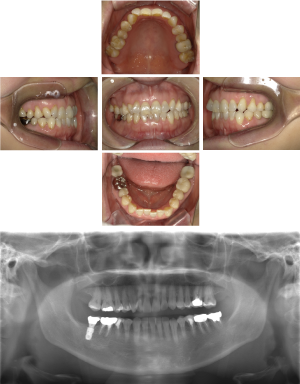

50代 女性 インプラント治療(GBR・ソケットリフト)

| 年代・性別 | 50代・女性 |

|---|---|

| 主訴 | Brの歯が取れそうなため、インプラントに変えたい。 |

| 部位 | 左下567 左上④5⑥ 右上67 |

| 治療期間 | 約3年9ヶ月 |

| 費用 | ¥3,224,500(税込) |

| 副作用・リスク |

|